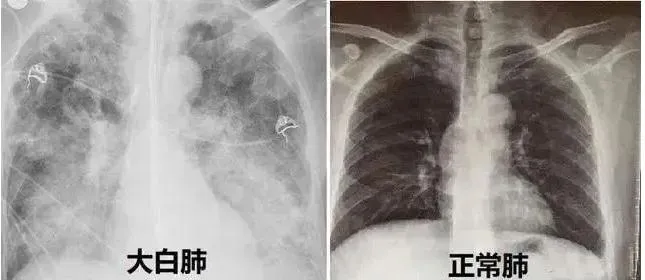

新冠

covid

大白肺